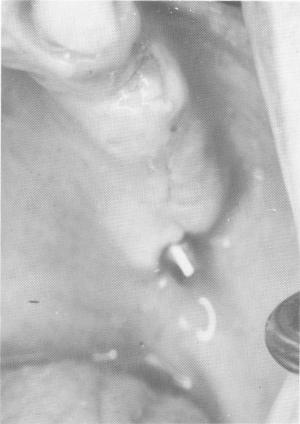

Fig. 15-46. Ten days after insertion of implant showing uneventful healing.

5 Uneventful healing after insertion of upper endosseous blade implant